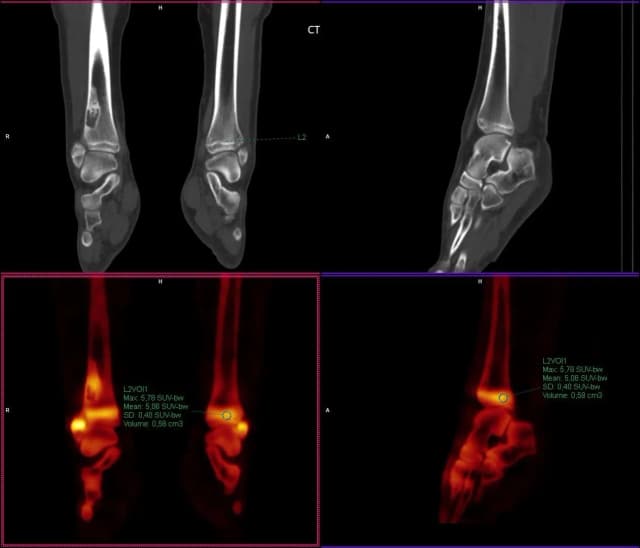

Co oznacza SUV w badaniu PET i jak wpływa na diagnozę chorób

Poznaj, co oznacza SUV w badaniu PET i jak wpływa na diagnozę chorób. Dowiedz się, jak wartości SUV pomagają w identyfikacji nowotworów i monitorowaniu terapii.